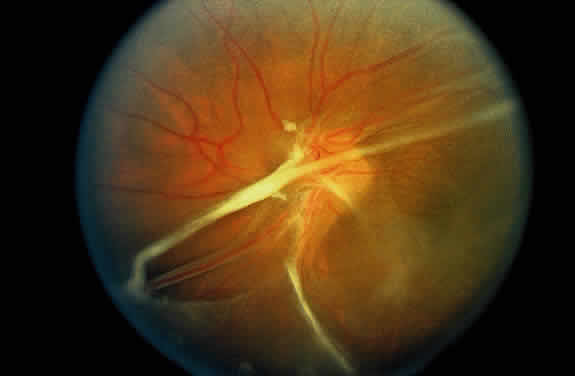

Signs of ocular inflammation are commonly encountered in Eales' disease, especially early in its course. Vascular sheathing is seen in most patients (Fig. 1). The degree of sheathing ranges from thin white lines on both sides of the blood column to thick heavy exudative sheathing. Areas of sheathing frequently leak dye with fluorescein angiography (Fig. 2). However, there is not a direct correlation between the regions of sheathing and staining.

Fig. 1. Vascular sheathing. A. Thin white lines surround retinal venule. B. Exudative-type arteriolar sheathing.

In the century since Henry Eales' observation of altered retinal veins, many investigators have described Eales' disease as a primary disease of altered retinal veins. Elliot and Harris suggest the term periphlebitis retinae for this disorder.4 However, recent reports suggest equal involvement of arteriolar and venular sheathing. Because of the evidence of arteriolar involvement (see Fig. 1B), this disease should be considered as a retinal vasculitis or vasculopathy. Others have used the term primary retinal perivasculitis.8 Cystoid macular edema, vitreal cells, keratic precipitates, and cell and flare in the anterior chamber have been observed in patients with Eales' disease.3